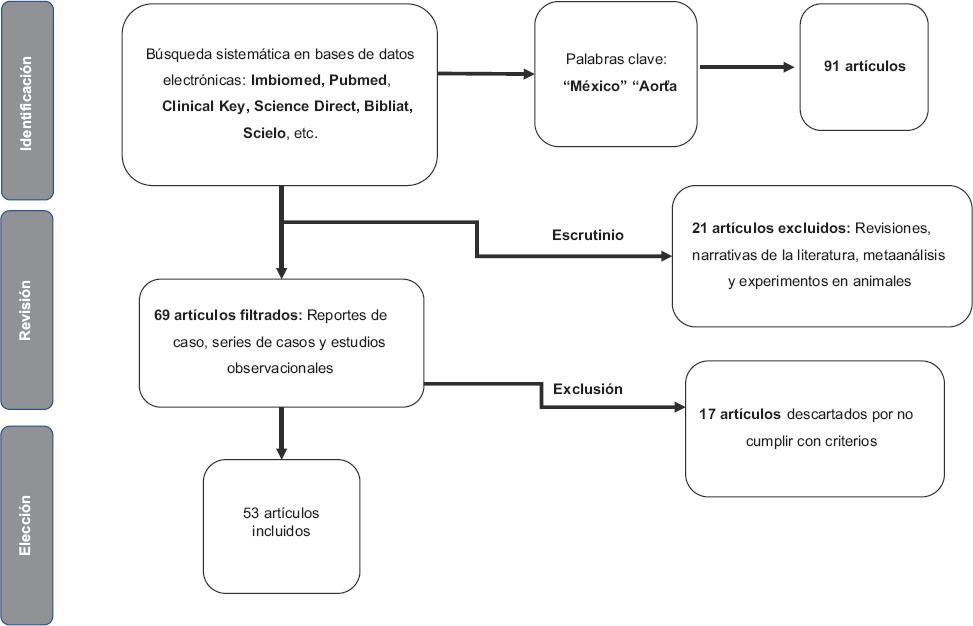

Se realizó una búsqueda sistemática en las bases de datos electrónicas PubMed (www.ncbi.nlm.nih.gov/pubmed), Imbiomed (www.imbiomed.com.mx), Clinical Key (http://www.clinicalkey.com), Bibliat (www.bibliat.unam.mx/es/), Scielo (www.scielo.org), Sage Journals (www.journals.sagepub.com), Science direct (www.sciencedirect.com) y con el motor de búsqueda de Google Académico. Como palabras clave se utilizaron los términos “México” y “aorta”.

En la Figura 1 se esquematiza el proceso de la revisión sistemática de la literatura. Se seleccionaron únicamente los artículos realizados en México y se excluyeron los relacionados con valvulopatía aórtica.